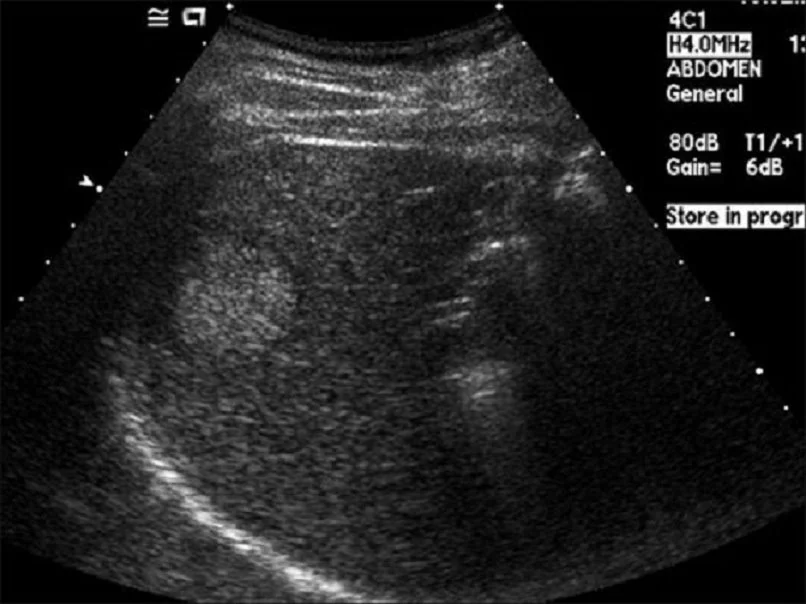

간암은 원격 전이가 된 뒤에 발견하면 5년 생존율이 3%에 그치지만 조기에 진단되면 약 50%로, 절반은 완치가 가능하기 때문에 대한 간암학회에서도 조기 발견을 강조하고 있습니다. 특별한 증상이 없어도 정기검진은 해야 합니다. 특히 고위험군인 B형 간염 보유자, C형 간염 보유자, 알코올성 간염, 간경변증이 있으신 분들은 꼭 6개월에 한 번씩 혈액검사와 복부초음파 검사를 하시길 바랍니다.